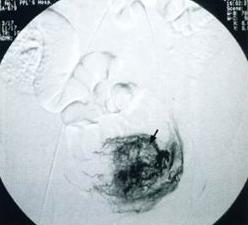

納博特囊腫超聲圖像示:

(1)本組彩色都卜勒顯示宮區宮旁血流豐富。

(2)本組液性暗區最大直徑18mm,最小直徑5mm,伴有子宮肌瘤7例(占14%),卵巢囊腫5例(占10%),盆腔積液10例(占20%),輸卵管積水2例(占4%),子宮次切術後1例(2%)。

(3)子宮頸肥大18例(占37%)。宮頸厚度在30mm以上,個別達到36mm。部分宮頸回聲可增強。

(4)頸部可見單或多個圓形或橢圓形液性暗區。單發19例(占39%),多發30例(占61%),邊界清晰,後方均伴有增強效應,其中5例還伴有囊壁鈣化。

分析:陰道超聲能彌補婦檢的不足,而且其對檢查者又具有操作簡便、診斷準確、針對性強、無創傷等優點。本組聲像圖具有一般囊腫聲像圖特徵,但其也應與子宮頸肌瘤等相鑑別。在聲像圖上子宮頸肌瘤為低回聲,CDFI示可有包膜血流,無囊腫特有的後壁增強效應。總之,陰道彩超能及時準確地查出已婚婦女的宮頸腺體囊腫,為臨床診斷及治療慢性宮頸炎提供了可靠依據宮頸腺體囊腫為宮頸慢性炎症所致,而臨床醫師僅能觀察到宮頸外口表面的小囊腫,但陰道彩超能查出宮頸深部腺體內所發生的瀦留性囊腫。納氏囊腫本身不引起患者自覺症狀,故未引起患者及臨床醫師的重視。隨著人們生活水平的提高,保健意識的增強;自從超聲診斷儀出現,體檢的婦女逐漸增多。上述49例均為體檢者,其中有宮頸炎的31例,有宮頸肥大18例,大致符合納氏囊腫的病因及病理。